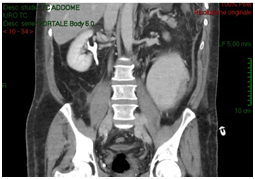

The CT-scan, targeted to a suspect of hemorrhage, did not have delayed phases. Patient received paracentesis with around 3200 cc fluid drained that was sent to microbiological examination. Result of bacteriological exam revealed infection by Proteus Mirabilis and he received target antibiotic therapy with resolution of septic status. In XXII post-operative day, for a progressive increase of serum creatinine we decided to perform an Uro-CT scan. The exam showed reduction of intraperitoneal fluid, right iliac side fluid collection with contrast enhancement during delayed phases; right ureter was not visible under fluid collection (Figure 3). We attempted to insert a ureteral stent in retrograde way but ureter resulted totally interrupted inside the fluid collection so the patient was undergone to explorative laparotomy and toilette of fluid collections. We found ureteral loss of substance of around 3 centimeter localized in anterior ureteral wall. We manufactured end-to-end ureteral anastomosis after positioning of ureteral stent seven French. We removed ureteral stent after 3 months and currently the patient is in follow-up with a good renal function as shown at last CT-scan after 10 months (Figure 4).

Figure 3: Post paracentesis Uro-CT scan showing reduction of intraperitoneal fluid, right iliac side fluid collection with contrast enhancement during delayed phases; right ureter was not visible under fluid collection.